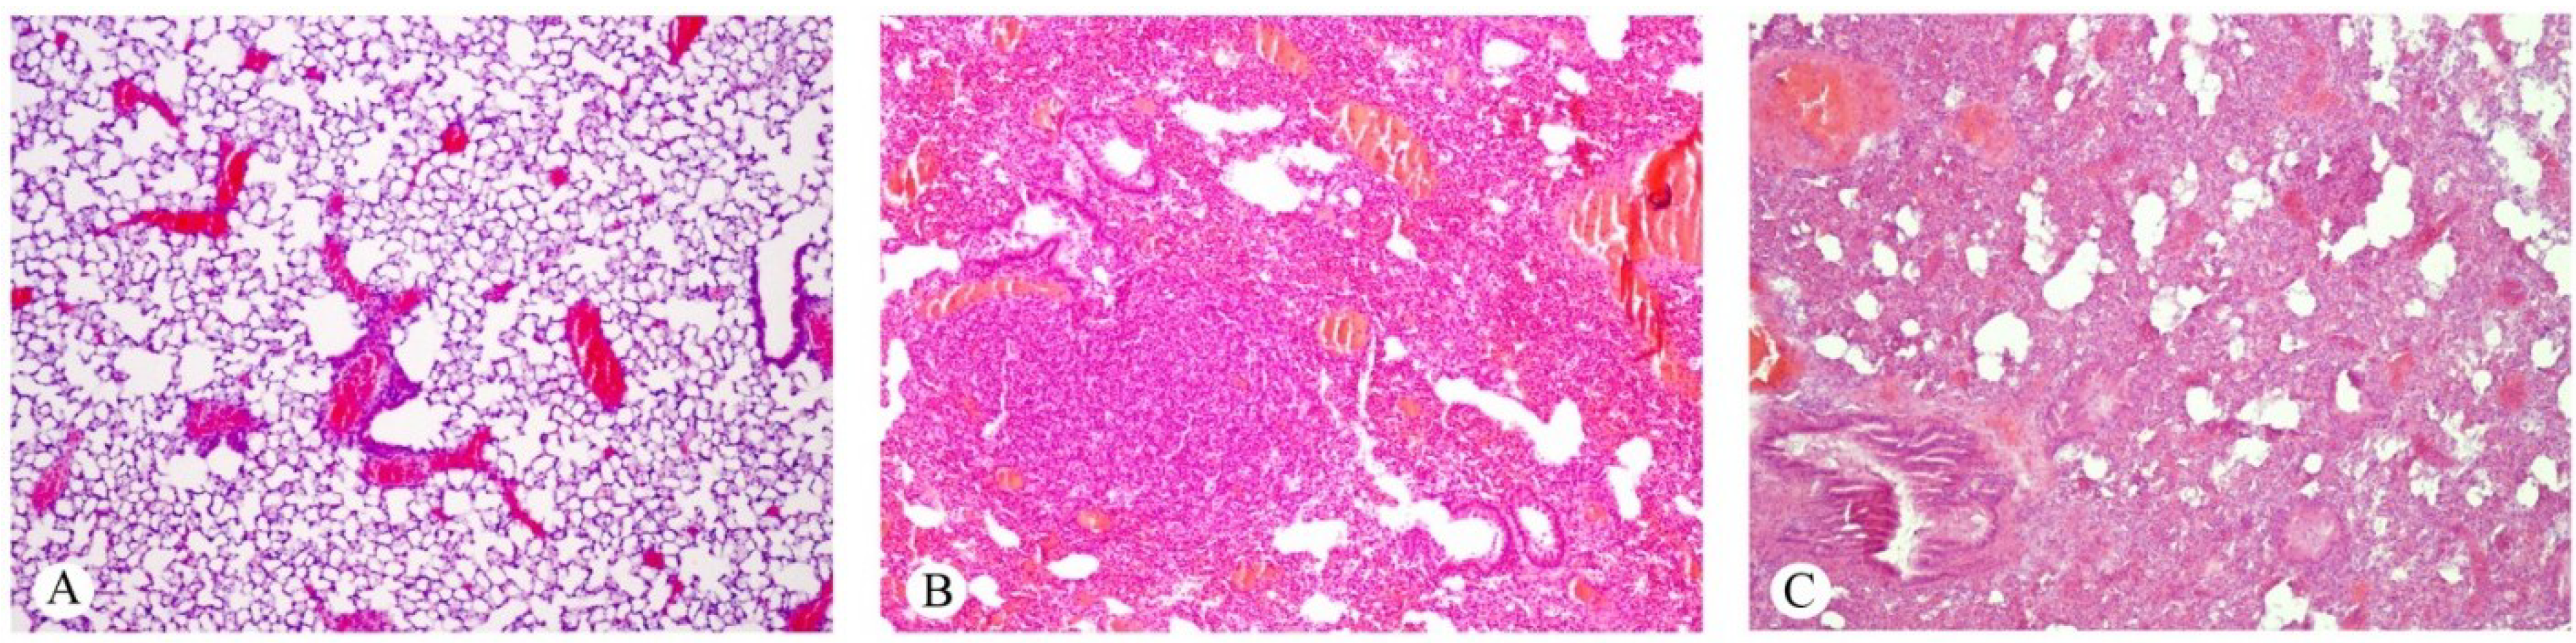

2.1. Effects on the Lung